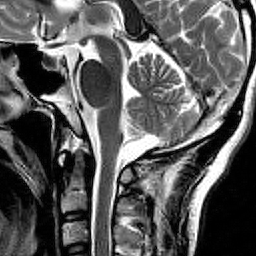

Hence both and should recover equally well. In the top row of Figure 1 we present the result of the flip test for a Gaussian random matrix. As is evident, the reconstructions and are comparable, thus indicating the RIP.

Having considered type II problems, let us now examine the flip test for a type I problem. As discussed, in applications such as MRI, X-ray CT, radio interferometry, etc, the matrix is imposed by the physical sensing device and arises from subsampling the rows of the DFT matrix .111In actual fact, the sensing device takes measurements of the continuous Fourier transform of a function . As discussed in BAACHGSCS ; BAGSAIEP , modelling continuous Fourier measurements as discrete Fourier measurements can lead to inferior reconstructions, and worse, inverse crimes. To avoid this, one must consider an infinite-dimensional compressed sensing approach, as in (2). See AHPRBreaking ; BAGSAIEP for details, as well as PruessmannUnserMRIFast for implementation in MRI. However, for simplicity, we shall continue to work with the finite-dimensional model in the remainder of this paper. Whilst one often has some freedom to choose which rows to sample (corresponding to selecting particular frequencies at which to take measurements), one cannot change the matrix .

It is well known that in order to ensure a good reconstruction, one cannot subsample the DFT uniformly at random (recall that the sparsifying transform is a wavelet basis), but rather one must sample randomly according to an appropriate nonuniform density AHPRBreaking ; Candes_Romberg ; Lustig ; WangAcre . See the bottom left panel of Figure 1 for an example of a typical density. As can be seen in the next panel, by doing so one achieves a great recovery. However, the result of the flip test in the bottom right panel clearly demonstrates that the matrix does not satisfy an RIP. In particular, the ordering of the wavelet coefficients plays a crucial role in the reconstruction quality. To explain this, and in particular, the high-quality reconstruction seen in the unflipped case, one evidently requires a new analytical framework.

Note that the flip test in Figure 1 also highlights another important phenomenon: namely, the effectiveness of the subsampling strategy depends on the sparsity structure of the image. In particular, two images with the same total sparsity (the original and the flipped ) result in wildly different errors when the same sampling pattern is used. Thus we conclude that there is no one optimal sampling strategy for all sparse vectors of wavelet coefficients.